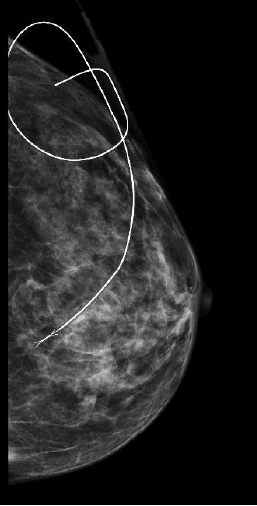

Cliché de mammographie avec repérage de la Tumeur et radiopièce correspondante

avec la tumeur au centre de l'image